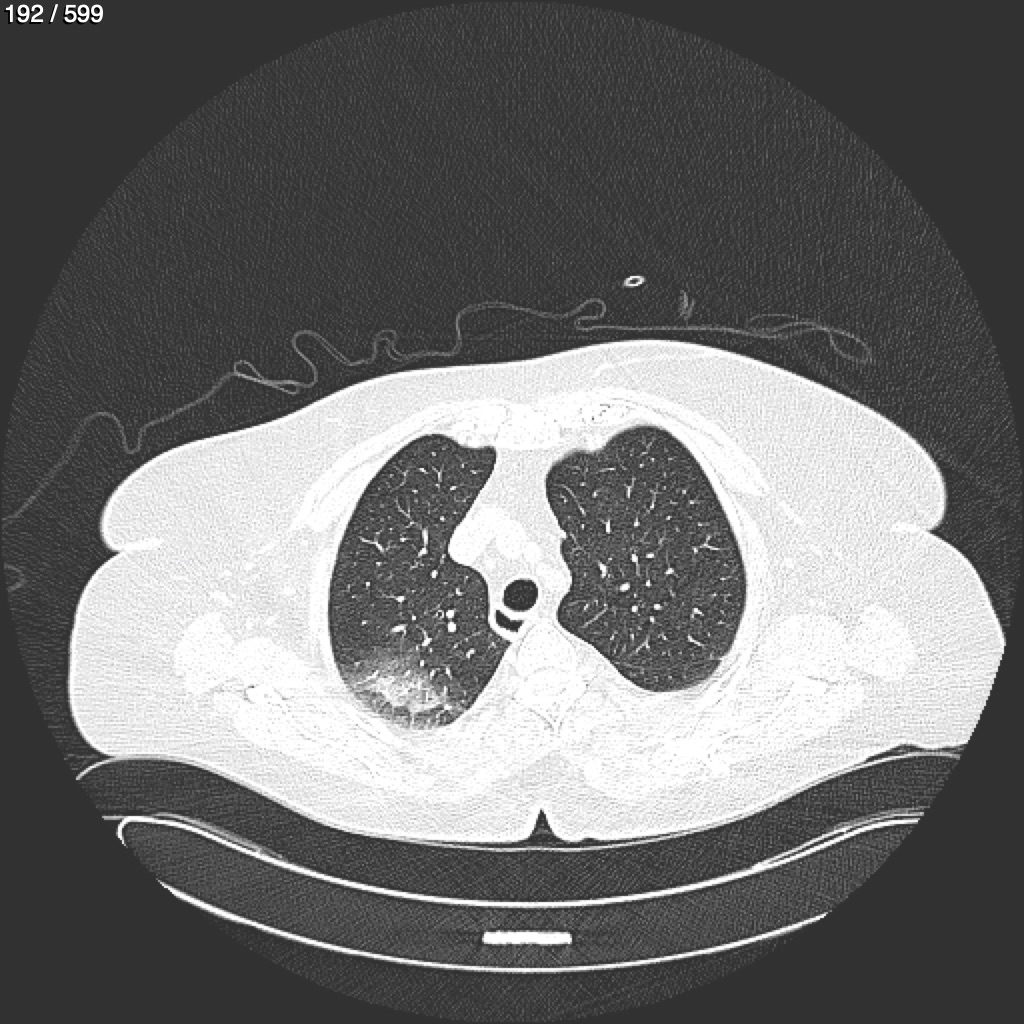

Home G​l​o​r​i​a​ ​G​l​a​d​y​s​ ​B​e​a​s​l​e​y​ ​-​ ​T​ó​r​a​x​ ​T​o​r​a​x​_​S​i​m​p​l​e​ ​(​A​d​u​l​t​o​)